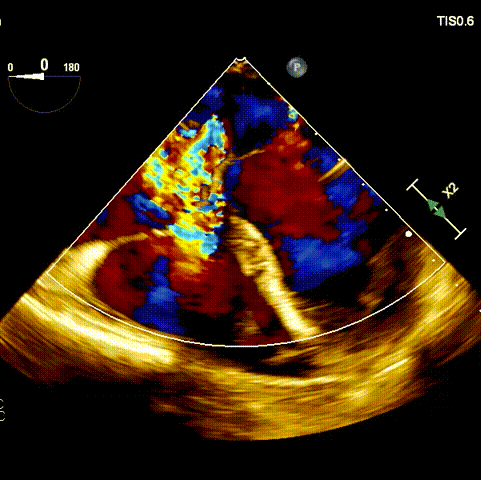

接受手術(shù)的為一名80歲男性,因“心悸2年,氣喘伴下肢水腫半年”入院。超聲心動(dòng)提示“極重度三尖瓣反流,右房及右室明顯擴(kuò)大,右心收縮功能輕度減低,左心收縮功能正常,肺動(dòng)脈壓力正常”?;颊咄瑫r(shí)合并有“持續(xù)性房顫”及“慢性心力衰竭”,病史持續(xù)2年,規(guī)律口服抗凝及強(qiáng)心、利尿治療治療效果不佳,癥狀持續(xù)。經(jīng)廈心心臟團(tuán)隊(duì)評(píng)估后,認(rèn)為患者三尖瓣極重度反流并伴有心衰表現(xiàn),長(zhǎng)期內(nèi)科藥物治療效果不佳,且患者高齡、外科手術(shù)風(fēng)險(xiǎn)高,因此決定采用微創(chuàng)經(jīng)頸靜脈LuX-Valve Plus三尖瓣置換系統(tǒng)為患者治療。

術(shù)前超聲

術(shù)后超聲